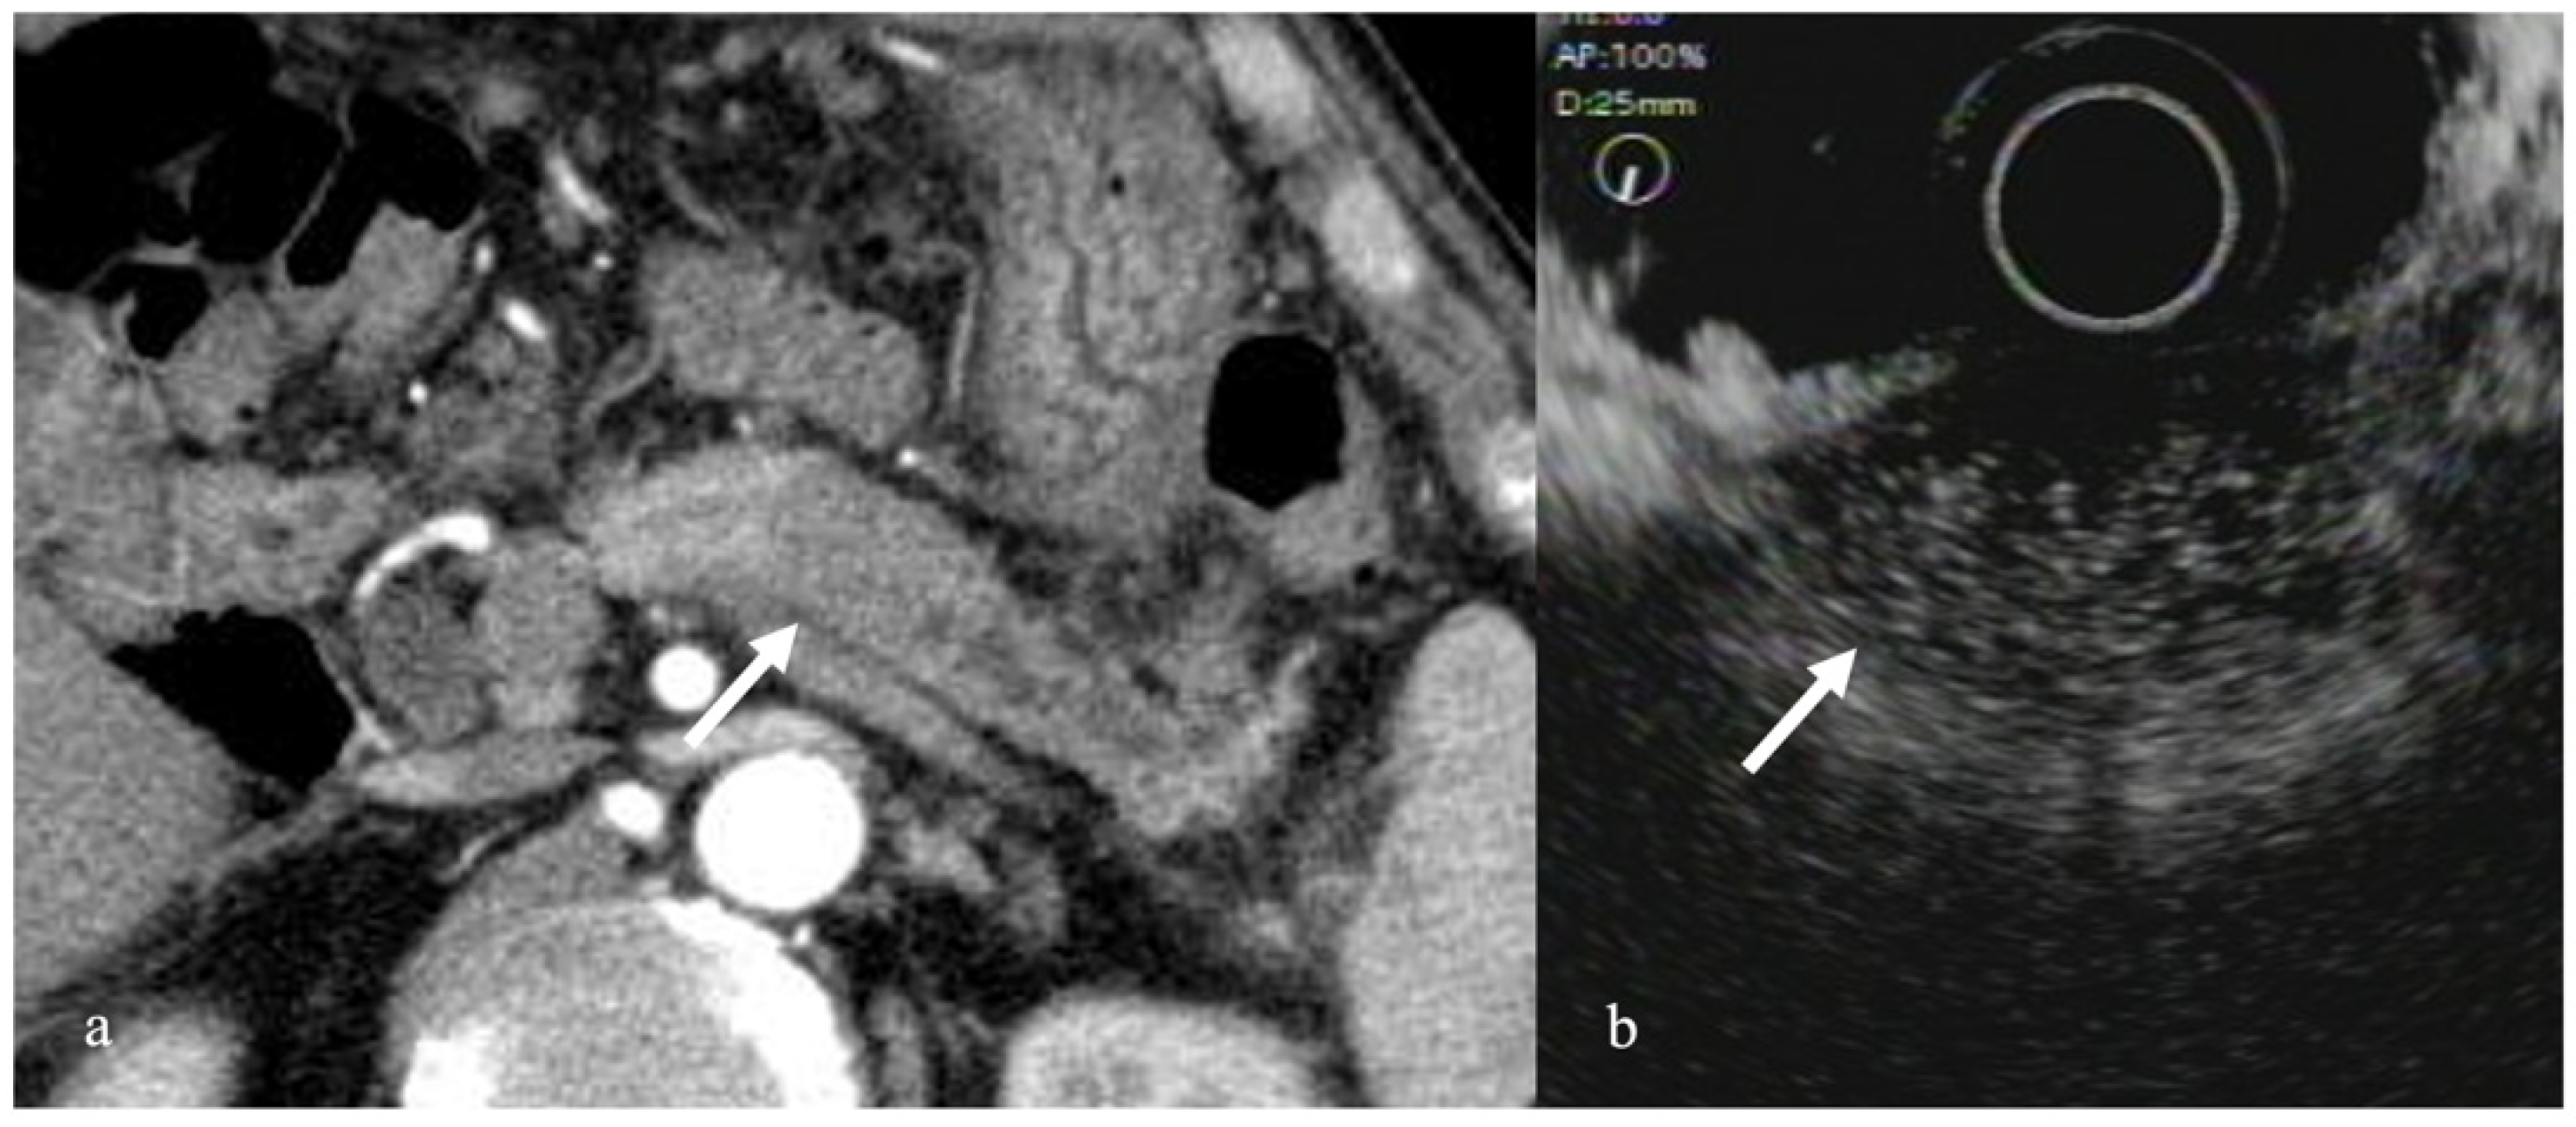

3.1. Solid Pancreatic Tumors

- Kitano, M.; Kudo, M.; Yamao, K.; Takagi, T.; Sakamoto, H.; Komaki, T.; Kamata, K.; Imai, H.; Chiba, Y.; Okada, M.; et al. Characterization of small solid tumors in the pancreas: The value of contrast-enhanced harmonic endoscopic ultrasonography. Am. J. Gastroenterol. 2012, 107, 303–310. [Google Scholar] [CrossRef] [PubMed]